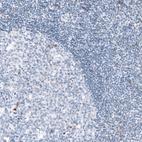

Immunohistochemical staining of human kidney shows strong membranous positivity in cells in glomeruli.